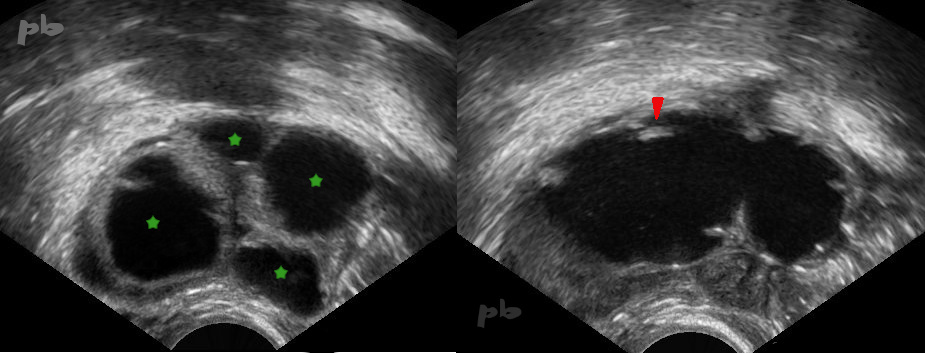

3 – Hydrosalpinx bilatéral

Echographie endovaginale.

Coupe transversale des 2 trompes.

Petites images pseudo-végétantes (![]() ) au sein de la lumière tubaire, de répartition régulière, donnant l’aspect classique de « roue dentée », caractéristiques de l’hydrosalpinx.

) au sein de la lumière tubaire, de répartition régulière, donnant l’aspect classique de « roue dentée », caractéristiques de l’hydrosalpinx.

Elles correspondent aux plis muqueux.

TD = trompe droite

TG = trompe gauche

3 – Bilateral Hydrosalpinx

Transvaginal ultrasound. Transverse section of both fallopian tubes. Small, pseudo-vegetative images ( ![]() ) within the tubal lumen, evenly distributed, creating the classic « gear wheel » appearance characteristic of hydrosalpinx. These correspond to mucosal folds.

) within the tubal lumen, evenly distributed, creating the classic « gear wheel » appearance characteristic of hydrosalpinx. These correspond to mucosal folds.

TD = Right fallopian tube

TG = Left fallopian tube

5 – Hydrosalpinx

(même patiente que 4)

Echographie endovaginale. Vidéo.

L’image de kyste ovarien (★) est en réalité en continuité avec l’autre structure liquidienne, ce que montre bien ce balayage échographique.

L’ovaire est distinct (★).

Il s’agit donc d’un hydrosalpinx, sans kyste ovarien associé. La portion la plus dilatée correspondant à la région ampullo-pavillonnaire.

5 – Hydrosalpinx (Same patient as image 4)

Transvaginal ultrasound. Video.

The apparent ovarian cyst (★) is actually continuous with the other fluid-filled structure, as demonstrated by this ultrasound sweep. The ovary is distinct (★). This is therefore a hydrosalpinx, with no associated ovarian cyst. The most dilated portion corresponds to the ampullary-infundibular region.